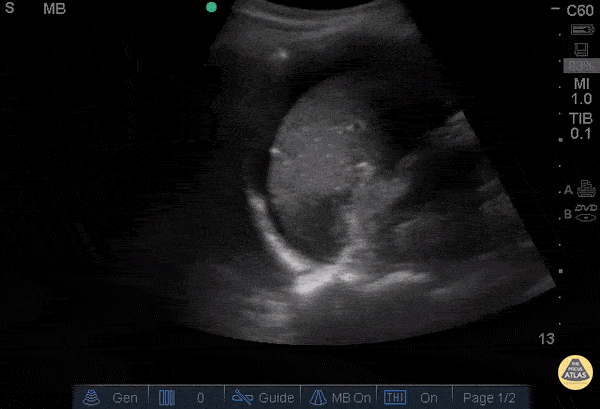

OB/Gyn - Positive FAST in LUQ - Ruptured Ovarian Cyst

28 year-old female was BIBEMS after a witnessed syncopal episode at home. The patient endorsed abdominal pain that started during intercourse that morning and had been getting worse. On arrival, the patient appeared pale and diaphoretic. The patient’s FAST exam was performed immediately and showed free fluid in the RUQ and LUQ. The suprapubic view showed a large pelvic hematoma. The patient was evaluated by the GYN service and was taken emergently to the OR where she was found to have a ruptured cyst. Don't forget, the FAST can be used for more than trauma. Dr. Guru Shan and Dr. Catherine Bon - Kings County Emergency Medicine